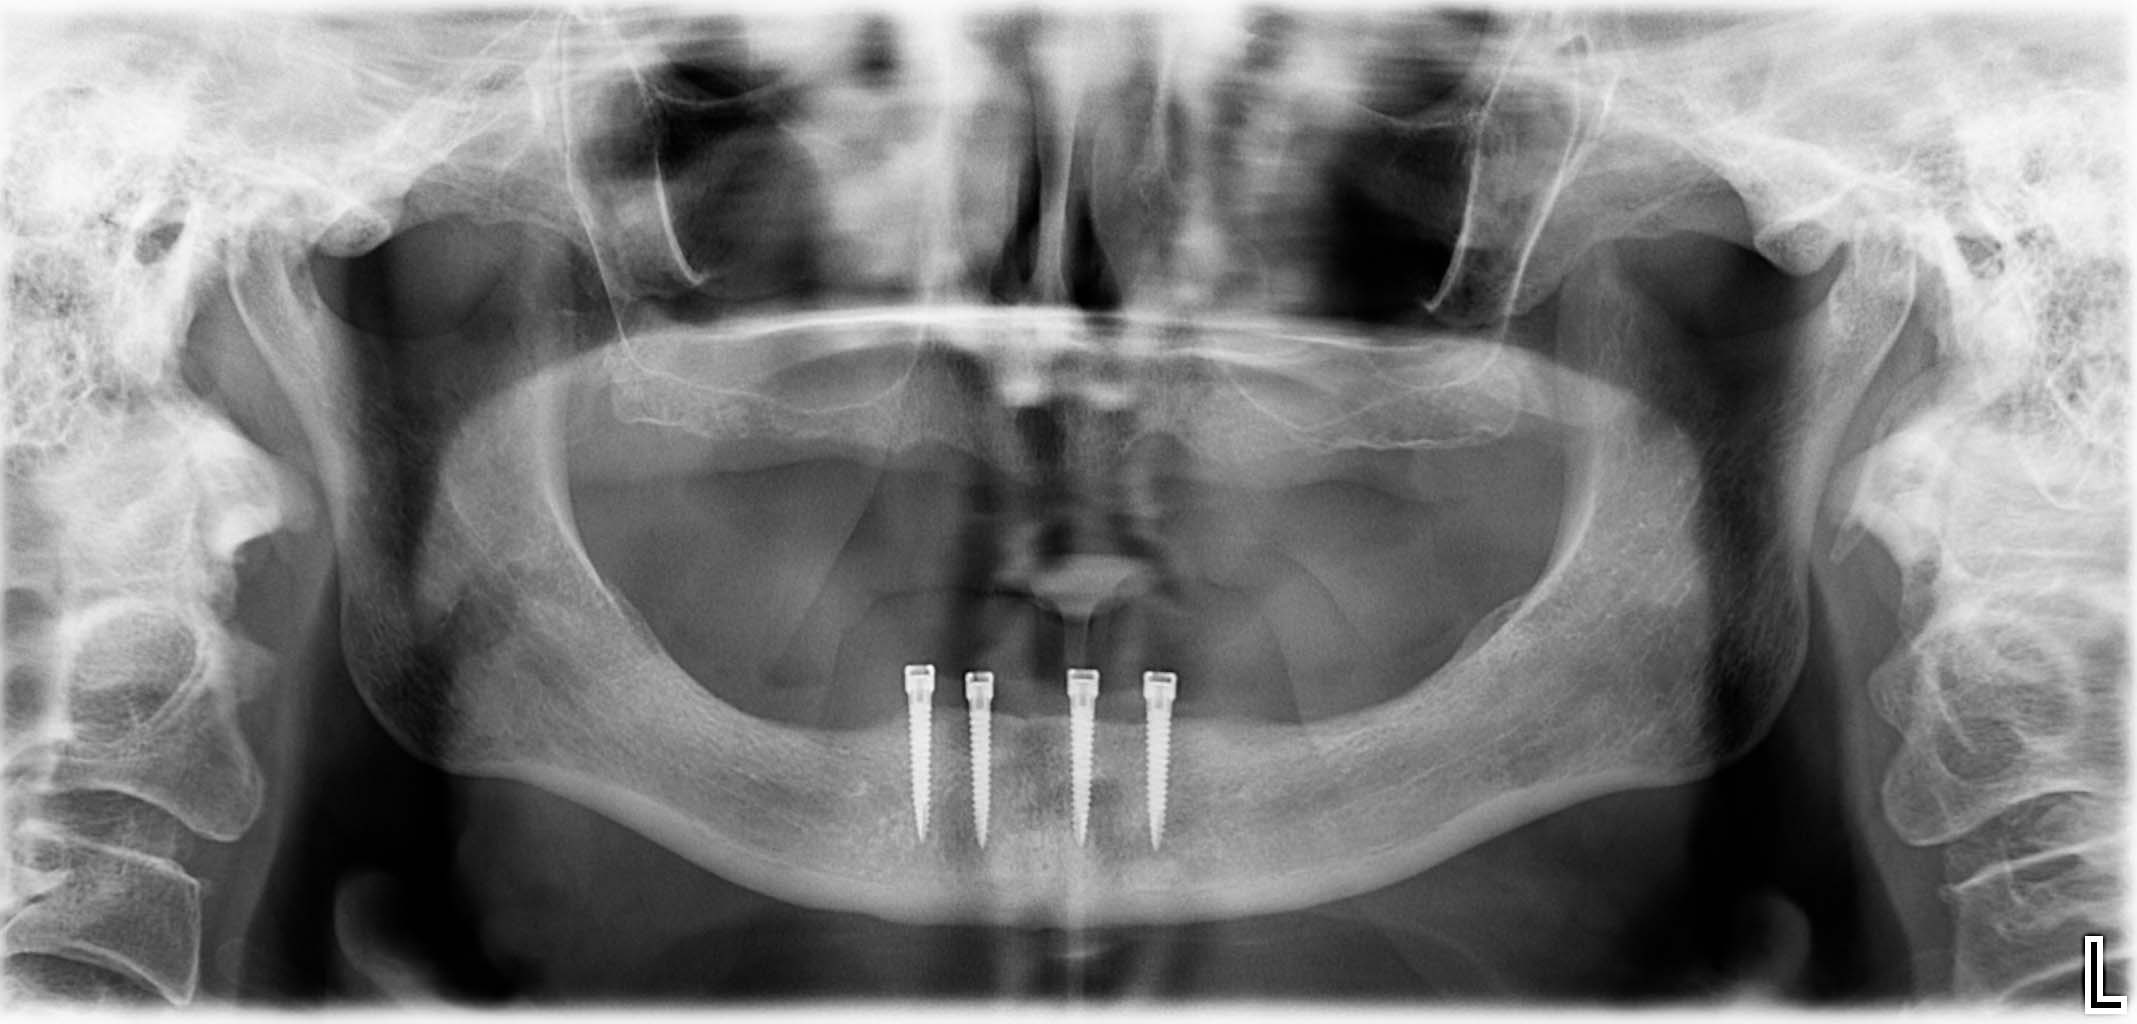

Erfolgreich implantierte Patientenfälle (klinische Fotos)